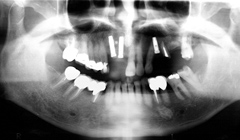

骨が無い部分にGBR(骨再生手術)を行い、インプラントと骨をくっつける

写真(2)

骨が再生されインプラントときちんとくっついている状態の写真です。